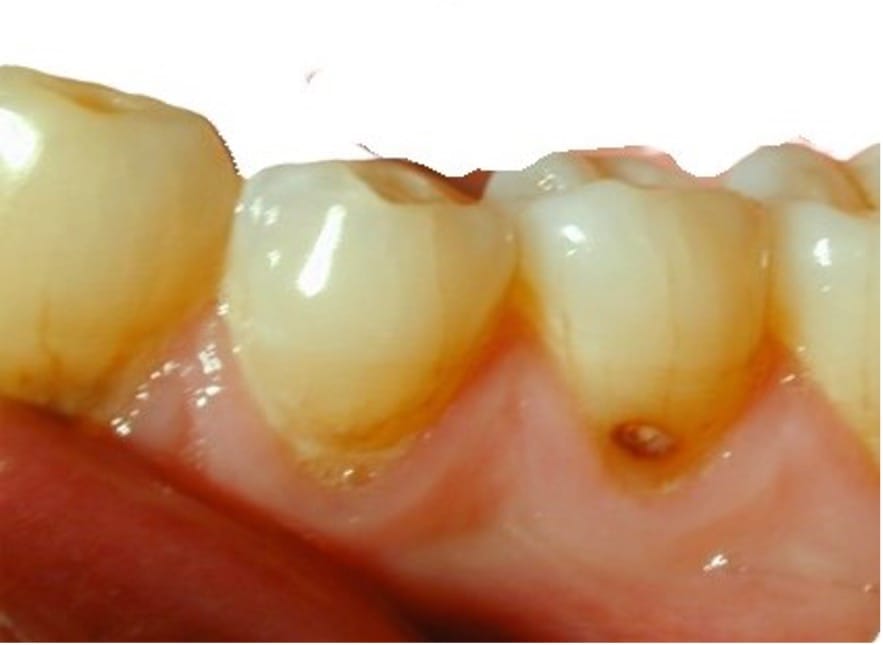

- Applicera SDF med en mikroborste direkt på kariesangreppet (Figur 1). En droppe (25 μL) räcker till att ”pensla” upp till fem tänder

- Låt SDF absorberas och torka in i minst 1 minut. Undvik salivkontakt

- Följ upp behandlingen inom 2-4 veckor för att bedöma kavitetens aktivitet. Har den inte mörknat och/eller hårdnat vid sondering kan behandlingen återupprepas